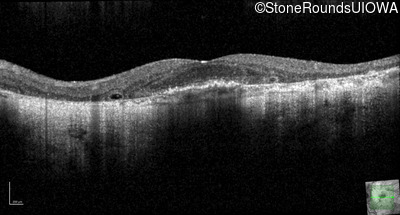

Age at visit: 51 years

This 51 year old woman first experienced some abnormality in her distance vision when she was 27 years old. She feels that her vision has been stable since that time.